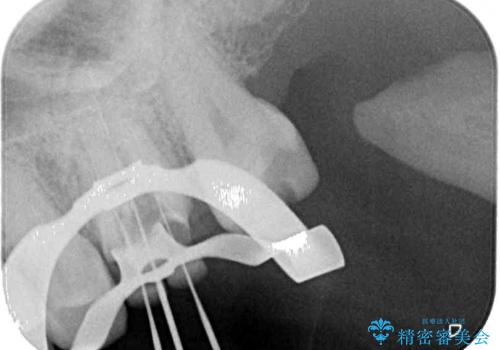

根管治療が必要と思えるような所見も認められませんでしたが、一緒に行いたいとの希望があったため、根管治療を行った上で補綴治療を行うこととしました。

- 根管治療により痛みや腫れがひかない事や、術後に痛みや腫れが生じる事、治療によるファイル破折やパーフォレーションなどの偶発症、術後の歯根破折を生じる可能性もあります